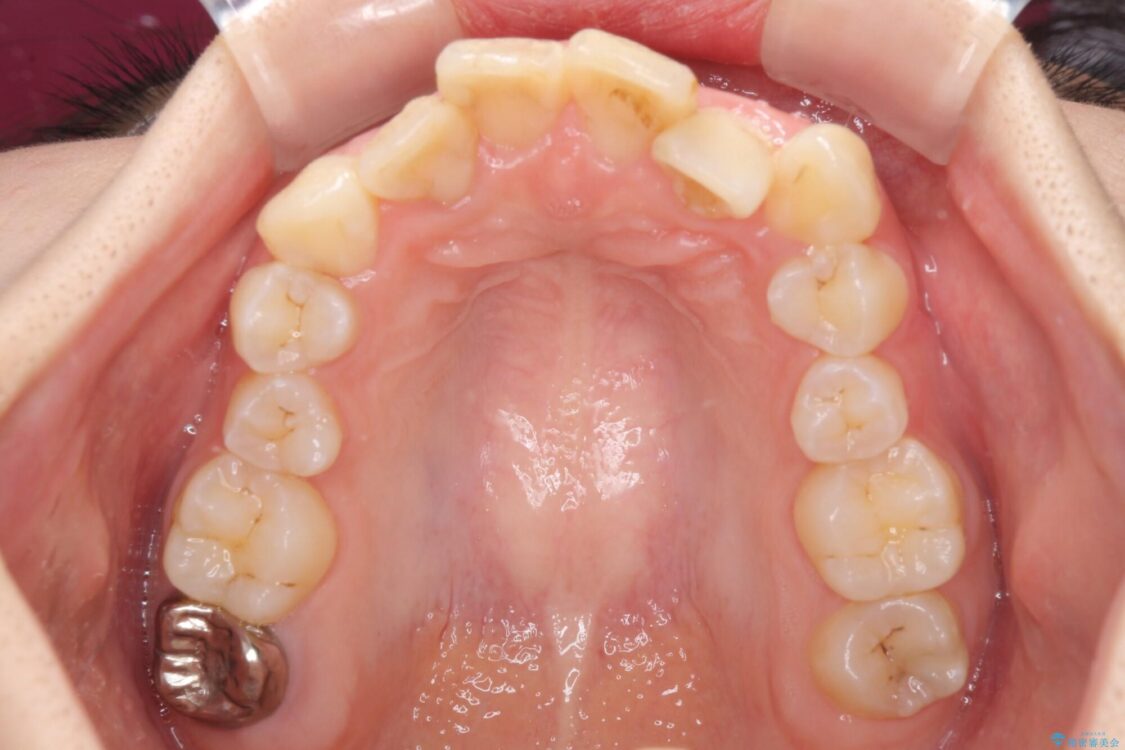

治療前

• デコボコと深い咬み合わせ ワイヤー装置での抜歯矯正 治療前画像

内側に倒れ込んだ歯や下の前歯が隠れてしまうほどの咬み合わせを改善したいとのことで来院された患者様です。

下顎の叢生を解消するために抜歯が必要であり、奥歯の咬み合わせや口元の印象から、上顎も同様に抜歯と判断し、上下左右の第1小臼歯4本抜歯してワイヤー装置にて矯正治療を行うこととしました。